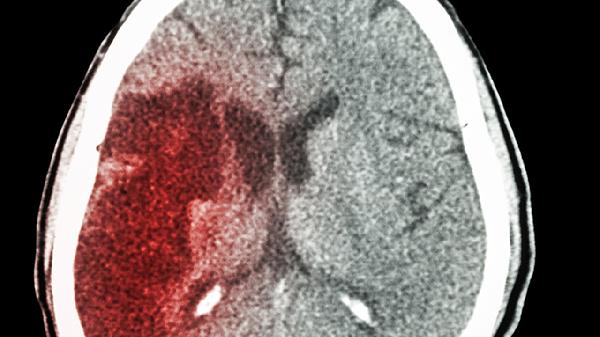

医生调查发现:脑梗患者若过早自行锻炼,半年内肢体或迎来4变化

脑梗后急着做康复训练?先别急着下床!康复科医生透露,太早开始自主锻炼可能适得其反。那些看似勤奋的复健动作,搞不好正在悄悄伤害你的身体。